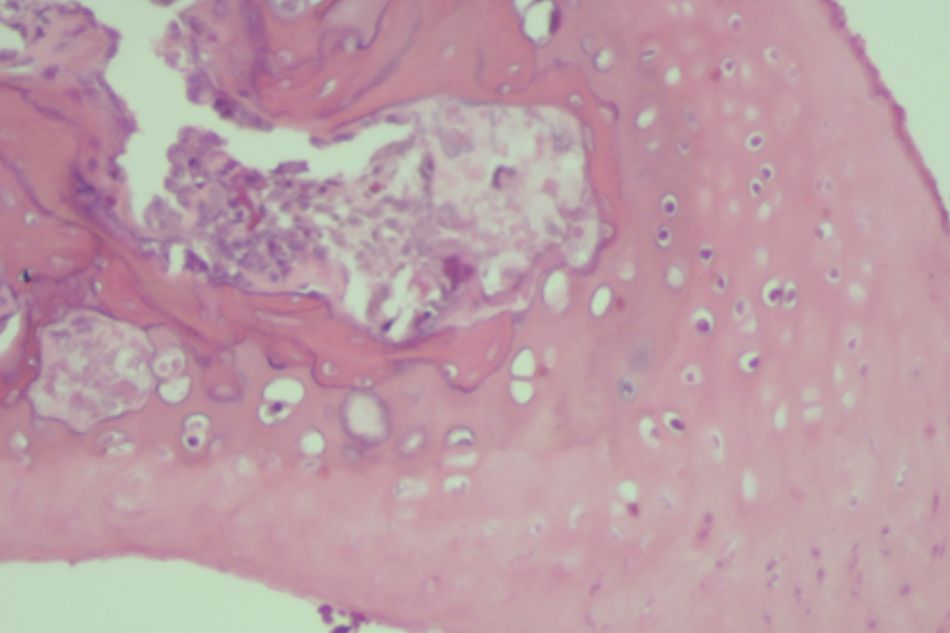

Figure 2.3. Knee joint sample in Group II (rat no.11)

Moderate subchondral bone and cartilage damage

Figure 2.4. Knee joint sample in Group II (rat no.12)